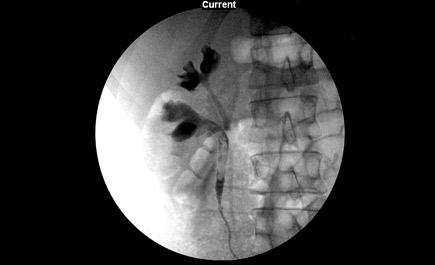

تمكن فريق جراحة المسالك البولية بمستشفى الدكتور سليمان الحبيب بالتخصصي من تشخيص وعلاج حالة طبية نادرة لمريضة تبلغ من العمر 45 عاماً تعاني من وجود حصوات بالحالب وأثناء إجراء الفحص الدقيق تبين أن لديها حالبين في الجهة اليمنى وآخرين في الجهة اليسرى Duplicated Ureter خلافاً لما هو معروف بأن الشخص الطبيعي يكون لديه حالبان فقط واحد بالجهة اليمنى والآخر باليسرى.

ذكر ذلك الدكتور علي الجعفر استشاري أمراض المسالك البولية الحاصل على الزمالة الألمانية في جراحة الكلى والمسالك البولية ورئيس الفريق الجراحي المعالج، وأضاف بأن المريضة كانت تعاني لعدة أشهر من آلام حادة متقطعة وبعد التشخيص بالفحوصات المخبرية والأشعة الطبقية المحورية (C.T. Scan) تبين وجود حصوتين في كل حالب بالجهة اليمنى يتراوح حجمهما بين (4 إلى 6) ملم.

وأفاد د. الجعفر بأنه تم دراسة حالة المريضة جيداً ووضع خطة علاجية تقتضي عمل منظار للحالب Ureteroscopy لتفتيت إحدى الحصوات بالليزر (Laser Lithotripsy)

أما الحصوة الموجودة بالحالب الآخر فتم التعامل معها بوضع «أنبوب» داخلي يعمل على توسيع الحالب وذلك لتضيقه الشديد مع الحفاظ على عدم انسداده مرة أخرى لضمان نزول البول من حوض الكلية إلى المثانة، بالإضافة إلى تفتيت الحصوة عن طريق استخدام تقنيات الموجات التصادمية (ESWL).